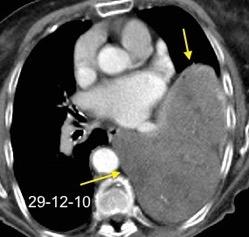

Nefrectomia derecha en 1996 por adenocarcinoma renal. Reseccion de metastasis pulmonar en LSI de carcinoma renal. Sospecha de nueva metástasis.

Granuloma de cuerpo extrano por hilo de sutura en situación cisural

Madan Ret al. Intrathoracic gossypiboma. AJR 2007/Anderson JM et al. FOREIGN BODY REACTION TO BIOMATERIALS. Semin Inmunol 2008/Okazaki M et al. Two cases of granuloma mimicking local recurrence after pulmonary segmentectomy. Journal of Cardiothoracic Surgery. 2020